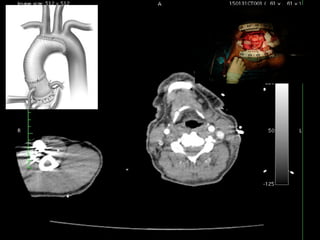

Mr HR, 65yo

Chest & Back Pain 4d before

admissions

Uncontroled hipertension,

DM

History (+) 6 month